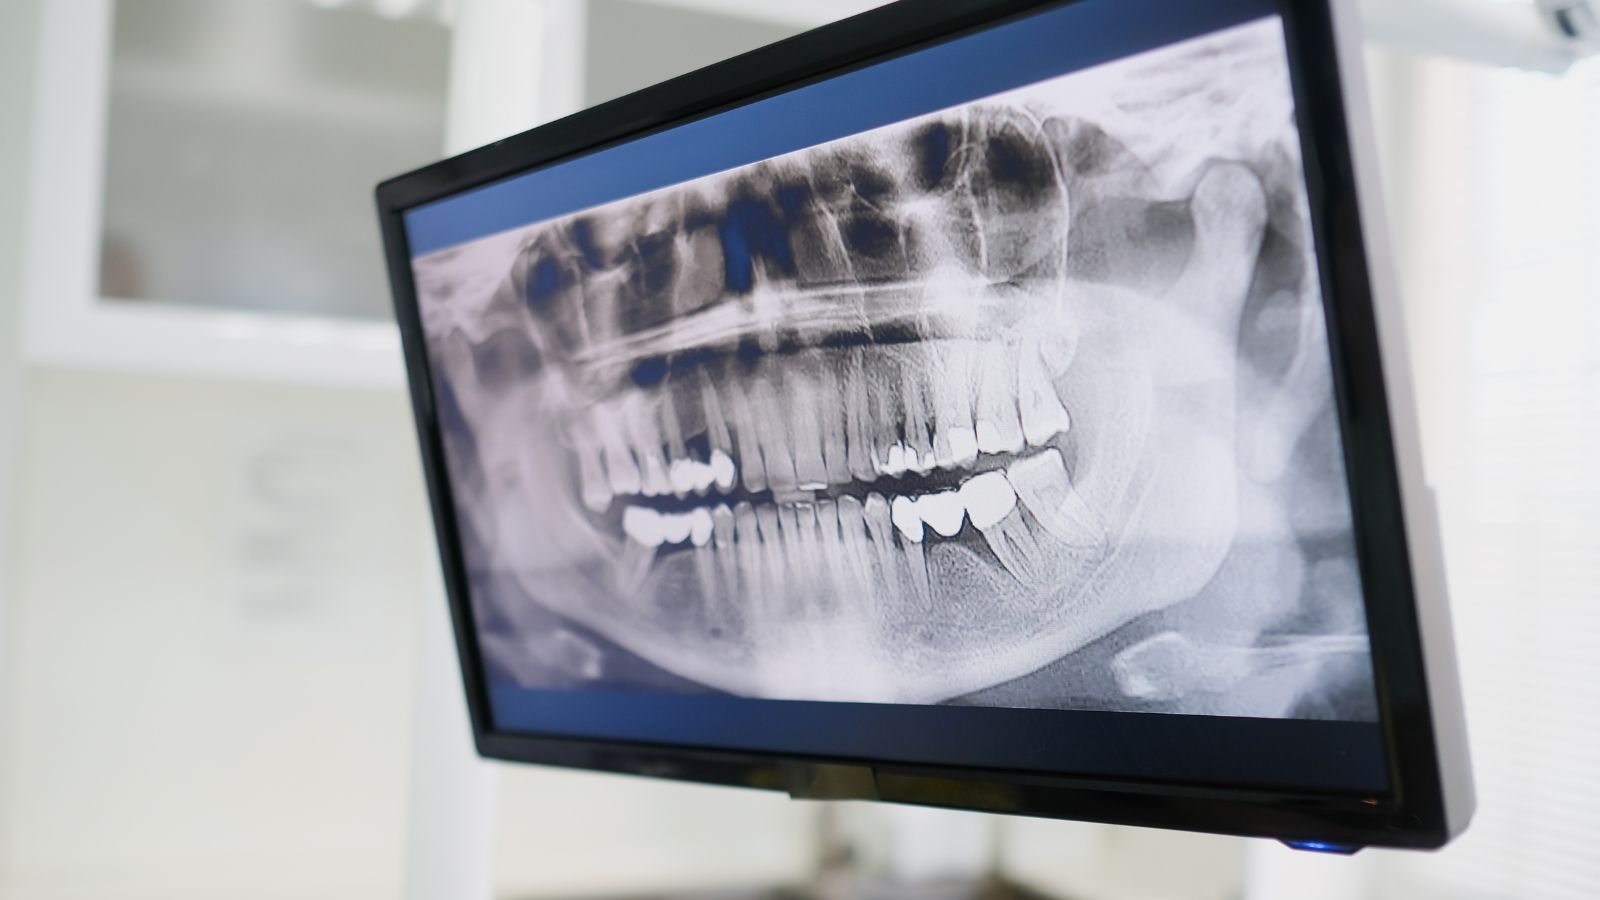

自由診療の根幹治療では、CTスキャンを使用して根幹の立体的な構造を把握します。

歯科用CTにより、根幹の数や形状を正確に診断し、治療計画を立てることができます。